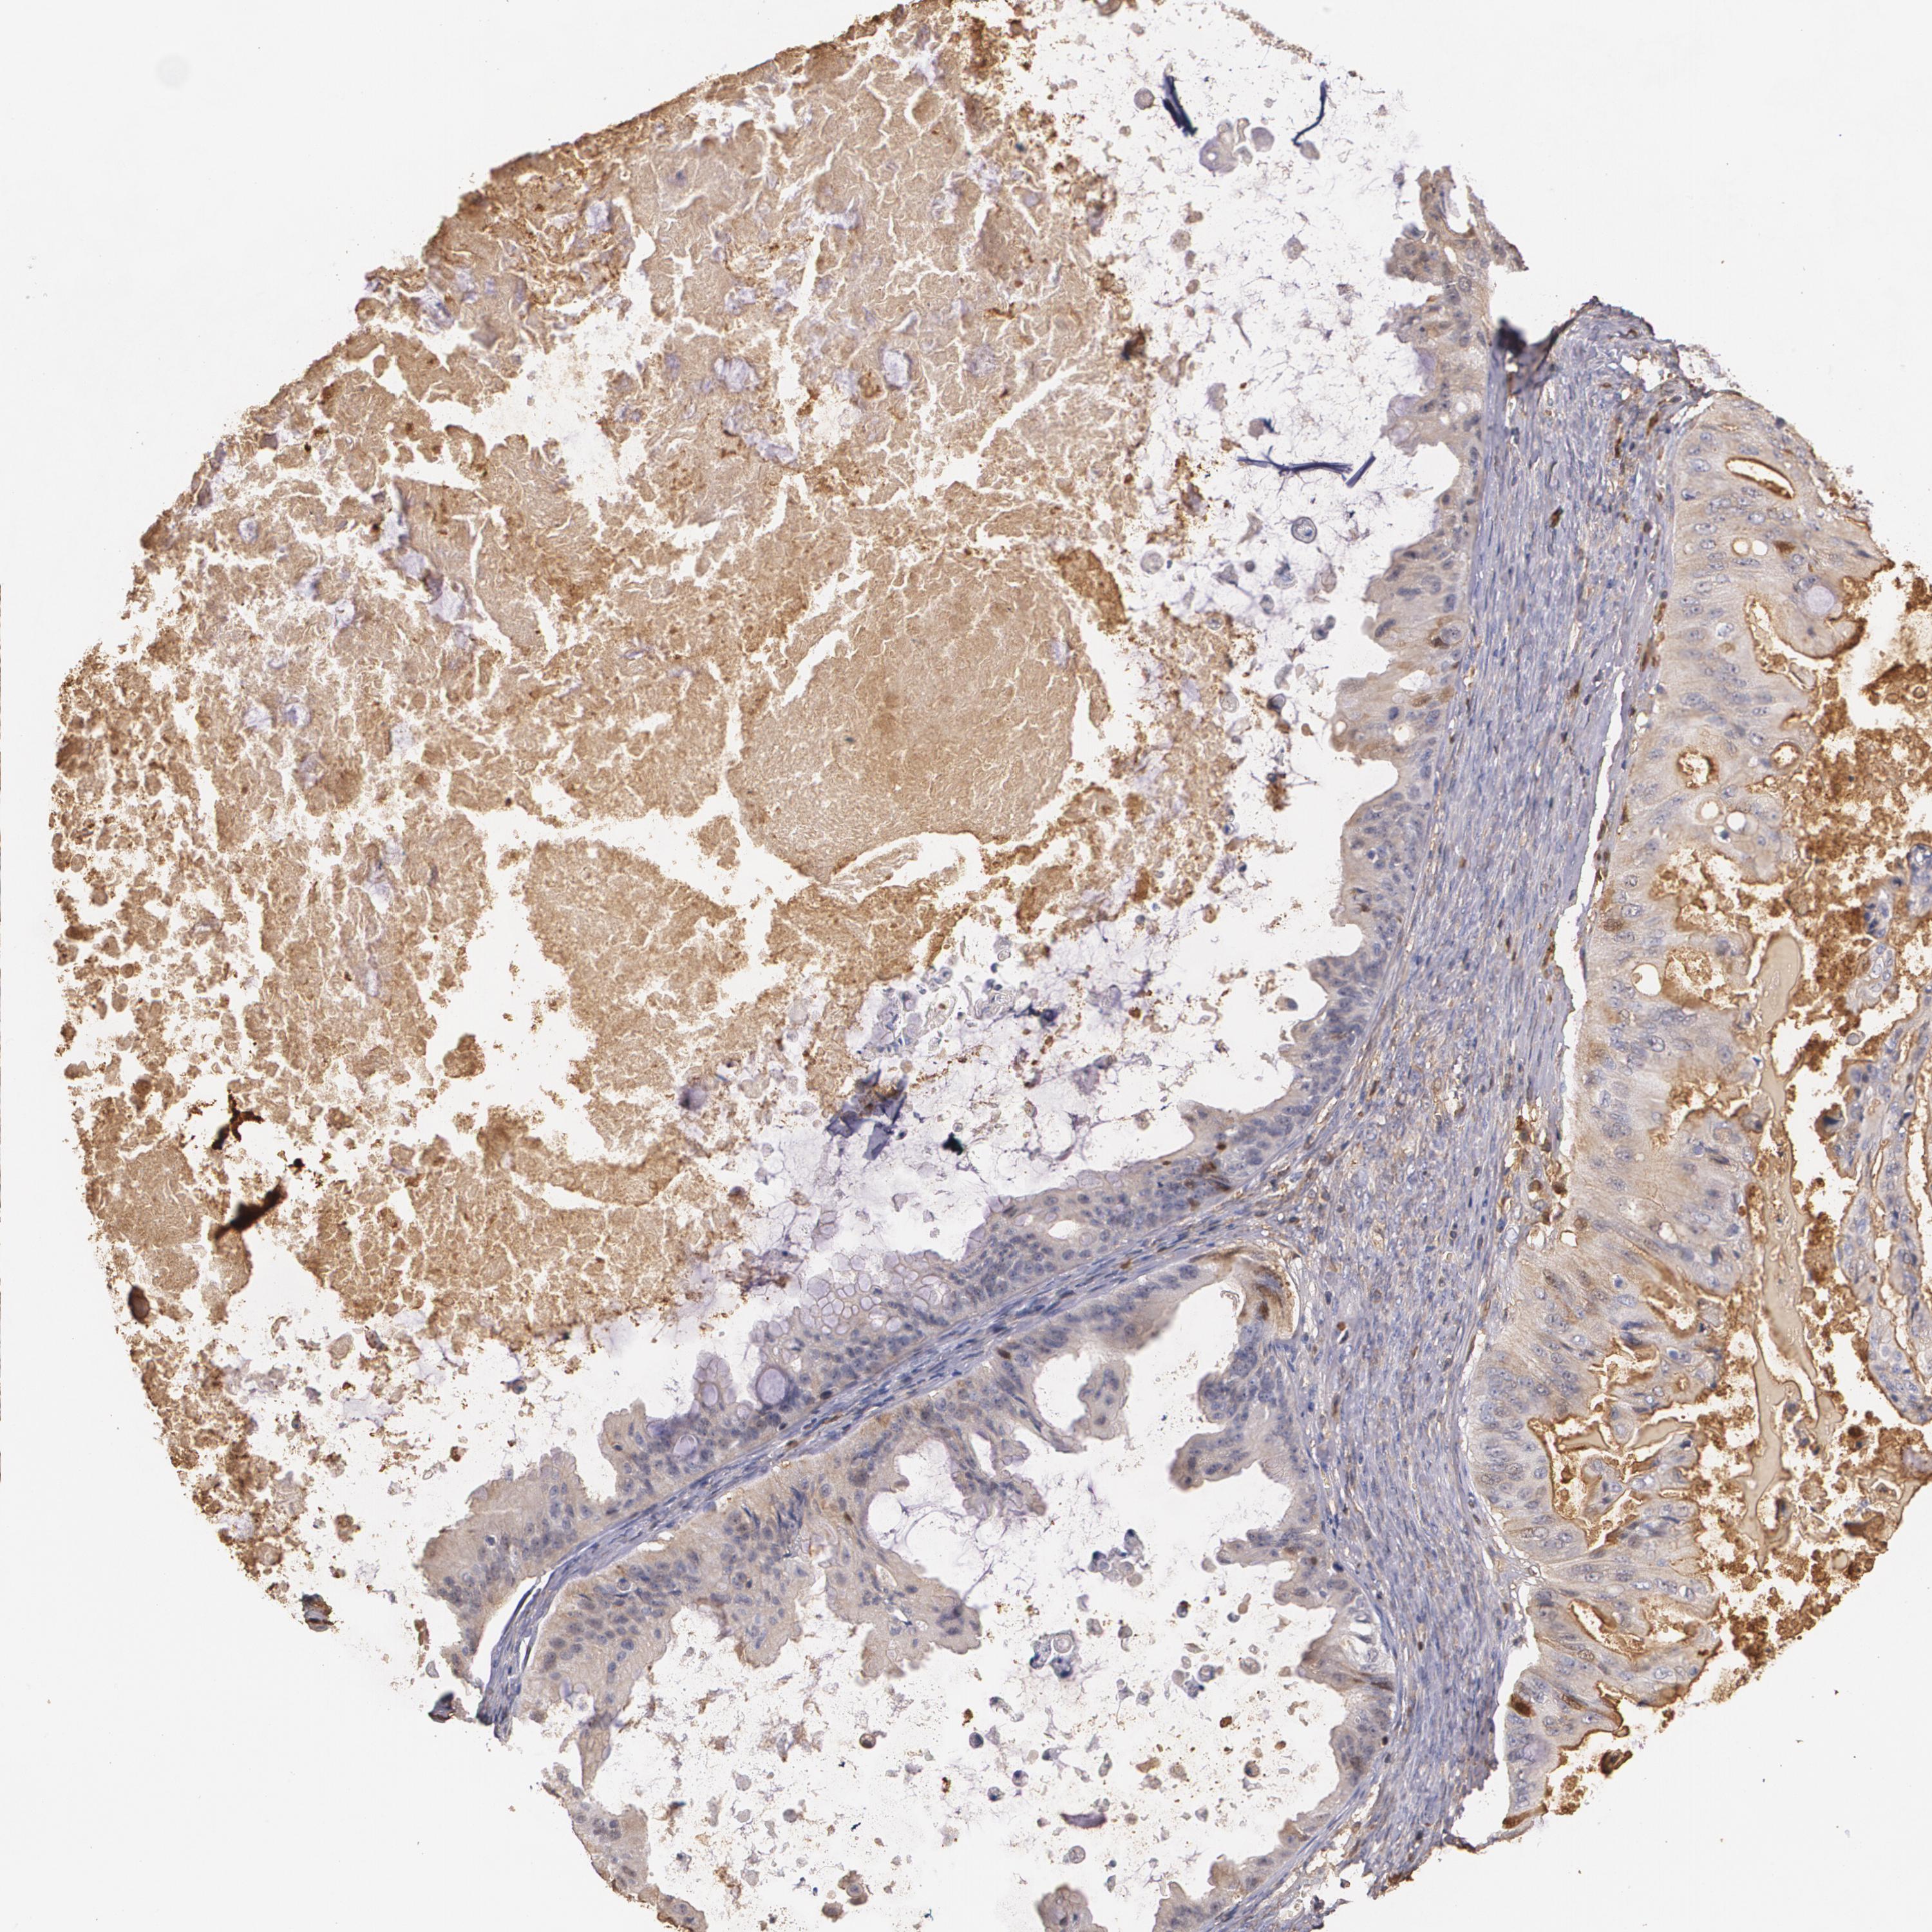

OVARIAN CANCER - Protein expressioni

A mouse-over function shows sample information and annotation data. Click on an image to view it in a full screen mode. Samples can be filtered based on level of antibody staining by selecting one or several of the following categories: high, medium, low and not detected. The assay and annotation is described here.

Note that samples used for immunohistochemistry by the Human Protein Atlas do not correspond to samples in the TCGA dataset.

Antibody stainingi

Antibody staining in the annotated cell types in the current human tissue is reported as not detected, low, medium, or high, based on conventional immunohistochemistry profiling in selected tissues. This score is based on the combination of the staining intensity and fraction of stained cells.

Each image is clickable and will lead to virtual microscopy that enables deeper exploration of all samples and also displays staining intensity scores, fraction scores and subcellular localization as well as patient and tissue information for each sample.

Antibody HPA001481

Staining

High

Medium

Low

Not detected

Intensity

Strong

Moderate

Weak

Negative

Quantity

>75%

75%-25%

<25%

None

Location

Nuclear

Cytoplasmic/membranous

Cytoplasmic/membranous,nuclear

Cystadenocarcinoma, serous, NOS

Cystadenocarcinoma, mucinous, NOS

Carcinoma, endometroid